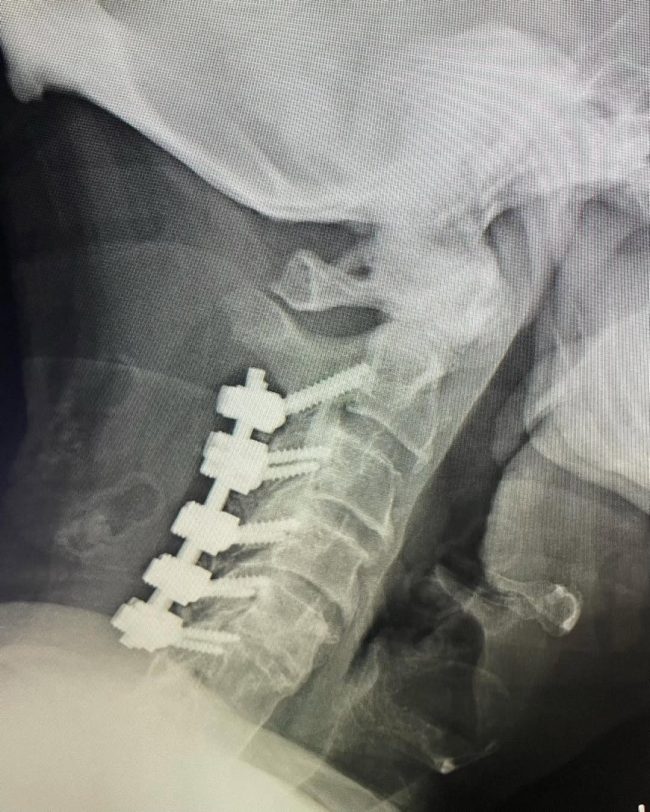

89-Year-Old with C5–6 Fracture-Dislocation: Surgical Stabilization

“Taking a call at a Level 1 trauma center is stressful and takes time away from family and a neurosurgeon’s precious free time. I was reminded recently why I still feel passionate about taking a Level 1 trauma call when I met this simply miraculous 89-year-old woman. She was involved in a motor vehicle collision…